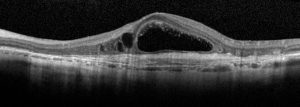

La tomografia a coerenza ottica (OCT) è un test di imaging non invasivo che utilizza le onde di luce per scattare foto della retina, e in particolare della macula. La macula è una parte della retina deputata alla visione a colori e ad alta definizione.

Con l’OCT possono essere analizzati e mappati tutti gli strati retinici, inoltre è possibile rilevare lo spessore retinico. Questi dati aiutano a effettuare una corretta diagnosi e a fornire delle indicazioni per il trattamento del glaucoma e delle patologie retiniche, malattie come la degenerazione maculare senile e la retinopatia diabetica.

Se in atto è presente o è stata presente una di queste condizioni retiniche è importante eseguire l’OCT.